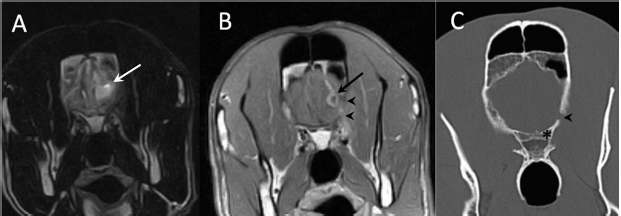

A 3-year-old female Great Dane was referred for acute onset behavioral changes (aggression and disorientation) of 2 weeks duration, and seizures from 24 hours prior to presentation. Physical examination revealed no abnormalities in body temperature, body condition score, heart rate, pulse quality, or cardiopulmonary auscultation. All lymph nodes were considered of normal size and no pain was elicited upon manipulation of the orbital, aural, or cranial musculature. Neither was there any history of dermatological or traumatic lesions in the eye, ear, or mouth. The neurological examination revealed the patient to be obtunded with decreased postural reactions and menace response worse in the left side. Neuroanatomic lesion localization was considered focal in the right prosencephalon with a possible increase in intracranial pressure. Hematological and serum biochemical analysis showed no abnormalities. Magnetic resonance imaging was performed using a low-field magnet (Airis Mate; Hitachi, Tokio, Japan). The study revealed a left-sided single frontal intra-axial lesion affecting gray and white matter adjacent to the internal capsule at the level of the optic canal (Fig. 1). The lesion presented signal homogeneity characterized by hyperintensity on T2W and FLAIR sequences and hypointensity in T1W sequences with peripheral enhancement after intravenous contrast administration (Fig. 1A and 1B). The lesion had a round shape with the greatest diameter of 2.84 cm. This enhancement was also recognized in the surrounding meninges following the brain surface following sulci. A small linear tract observed was directed dorsally from the lesion through the corona radiata (Fig. 1B). The lesion was associated with extensive perilesional vasogenic edema that worsened the mass effect characterized by a midline shift. The orbital and medial pterygoid muscles also showed an intense enhancement (Fig. 2). The wing of the presphenoid bone was thinner than the contralateral bone (Fig. 1B). A CT scan (Astelion 16, Toshiba, Tokio, Japan) was performed after MRI that allowed the identification of osteolysis in the presphenoid bone immediately dorsal to the orbital fissure (Fig. 1C). CT scan also revealed a hypoattenuating intra-axial lesion located in the left frontoparietal lobe together with diffuse hypoattenuation of tissues adjacent to the left optic nerve and the left pterygoid muscle. Finally, CSF analysis showed no abnormalities. On the basis of advanced radiological findings, the main differential diagnosis was an intracranial abscess due to the extension of the extracranial septic process through presphenoid bone. Because of rapid neurologic deterioration and suspected increased intracranial pressure, surgical excision was planned. A modified left rostrotentorial craniectomy was performed. Temporalis muscle and fascia were retracted, extending the incision cranially through the temporal line. Once the frontal and presphenoid bones were exposed an area of osteolysis was observed in the wing of the presphenoid bone immediately dorsal to the orbital fissure. The craniectomy (approximately 3 cm diameter) was centered on the osseous defect. A mucopurulent discharge presented immediately after the incision of the dura mater. A sample was collected for its microbiological study. The surgical site was flushed with sterile saline revealing the tip of a grass awn which was extracted from the brain parenchyma together with a small amount of purulent fluid (Fig. 3). After extensive flushing, the meninges were left open to allow drainage and the incision was closed as per routinely. Postoperative CT showed the correct location of the craniectomy and resolution of the abscess which was substituted by gaseous content but remained inside and on the dorsal surface of the frontal lobe (Fig. 4). Immediate postoperative therapy consisted of amoxicillin + clavulanic acid (Synulox 500, Zoetis Spain SL) 22 mg/kg PO, q8h; marbofloxacin (Marbocyl P80, Vetoquinol SA) 5 mg/kg PO, q24h; metronidazole (Flagyl 250, Sanofi-aventis SA) 15 mg/kg PO, q12h; prednisone (Prednisona Kern Pharma 30mg, Kern Pharma) 0.5 mg/kg PO, q12h; tramadol (Tramadol retard Combix 100 mg, Laboratorios Combix S.L.U) 2 mg/kg PO, q8h; famotidine (Famotidina Normon 40 mg; Laboratorios Normon SA) 0.7 mg/kg PO, q24h; and phenobarbital (Phenoleptil 100 mg, Le Vet BV) 2.5 mg/kg PO, q12h. Cultured samples were positive for Pseudomonas aeruginosa sensitive to ciprofloxacin, imipenem, and amikacin among other antibiotics. Based on these results, antibiotic therapy was changed to ciprofloxacin (Ciprofloxacino 500, Laboratorios Normon SA) 10 mg/kg PO, q12h and metronidazole 15 mg/kg PO, q12h for 2 months. Prednisone, tramadol, and famotidine were withdrawn and phenobarbital was maintained at 2.5 mg/kg q12h. Six-month post-operative revision magnetic resonance revealed no signs suggesting the existence of an inflammatory process (Fig. 5). In the area where the abscess had been located, a fluid-filled cavity suggesting being CSF was observed. One year follow-up revealed the patient had seizures every 3 months with neurological examination remaining normal. The patient died 2 years later of unrelated causes.

Fig. 3. Intraoperative view after left rostrotentorial craniectomy and durotomy above the orbital fissure. Note durectomy and the presence of a grass awn (arrows) overlying brain parenchyma once extracted from the frontal lobe.

Fig. 4. (A) Transverse and (B) 3D reconstruction postoperative CT images. Note increased defect on the presphenoid bone (arrows) immediately dorsal to the optic canal (arrowhead) and orbital fissure (dotted arrow). Also, note the presence of hypoattenuating content inside and over the dorsal surface of the frontal lobe (asterisks) compatible with air.

Fig. 5. (A) Transverse T2-weighted, (B) transverse post-contrast T1-weighted image, and (C) dorsal post-contrast T1-weighted image obtained 6 months after surgery. Note the absence of any contrast enhancement and residual lesion connecting the lateral ventricle (arrows). Also, note the defect in the presphenoid bone (arrowheads in C).